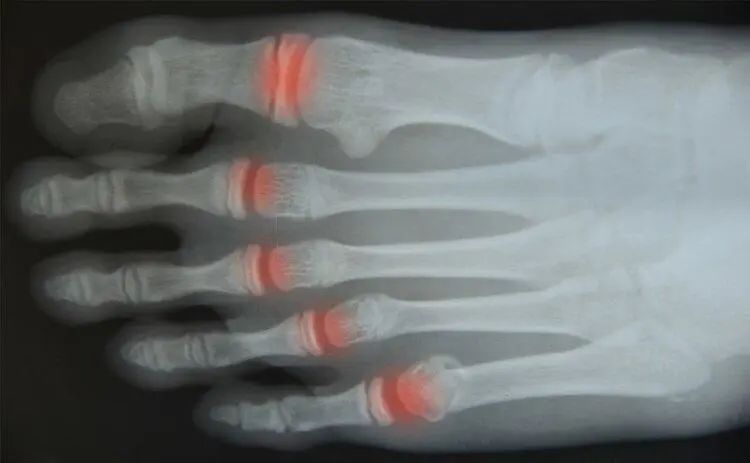

人类在长期进化的过程中,学会了“直立行走”,而骨骼也在不断适应这一特征。大部分中国人的第五个脚趾上只有2块趾骨,而欧美人有3块趾骨,是因为欧洲地区有山地丘陵,且他们的身材较为高大,在这种环境下奔跑和捕猎,脚掌需要更大的抓力,这让大部分欧美人保留了三块趾骨。

而亚洲的地势大部分比较平缓,且亚洲人的身材更为灵活,三块趾骨发挥的作用不大,久而久之,小脚趾的第三块趾骨就逐渐退化消失了。